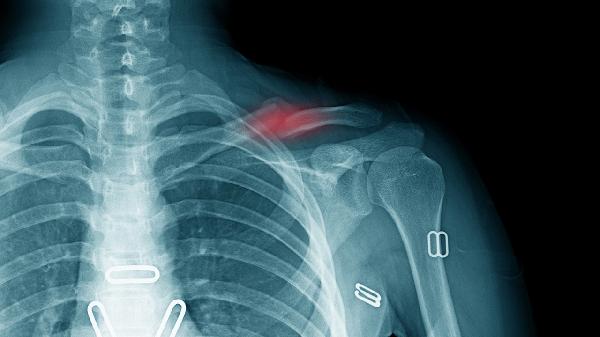

骨折恢复期除规范用药外,需保证每日500毫升牛奶或等量乳制品摄入,适量进食鱼类、豆制品补充优质蛋白。康复训练应分阶段进行,早期以肌肉等长收缩为主,6周后逐步增加负重。定期复查X线评估愈合进度,若出现患肢麻木、异常疼痛需及时复诊。避免吸烟饮酒及过量咖啡因摄入,以防影响骨组织修复。